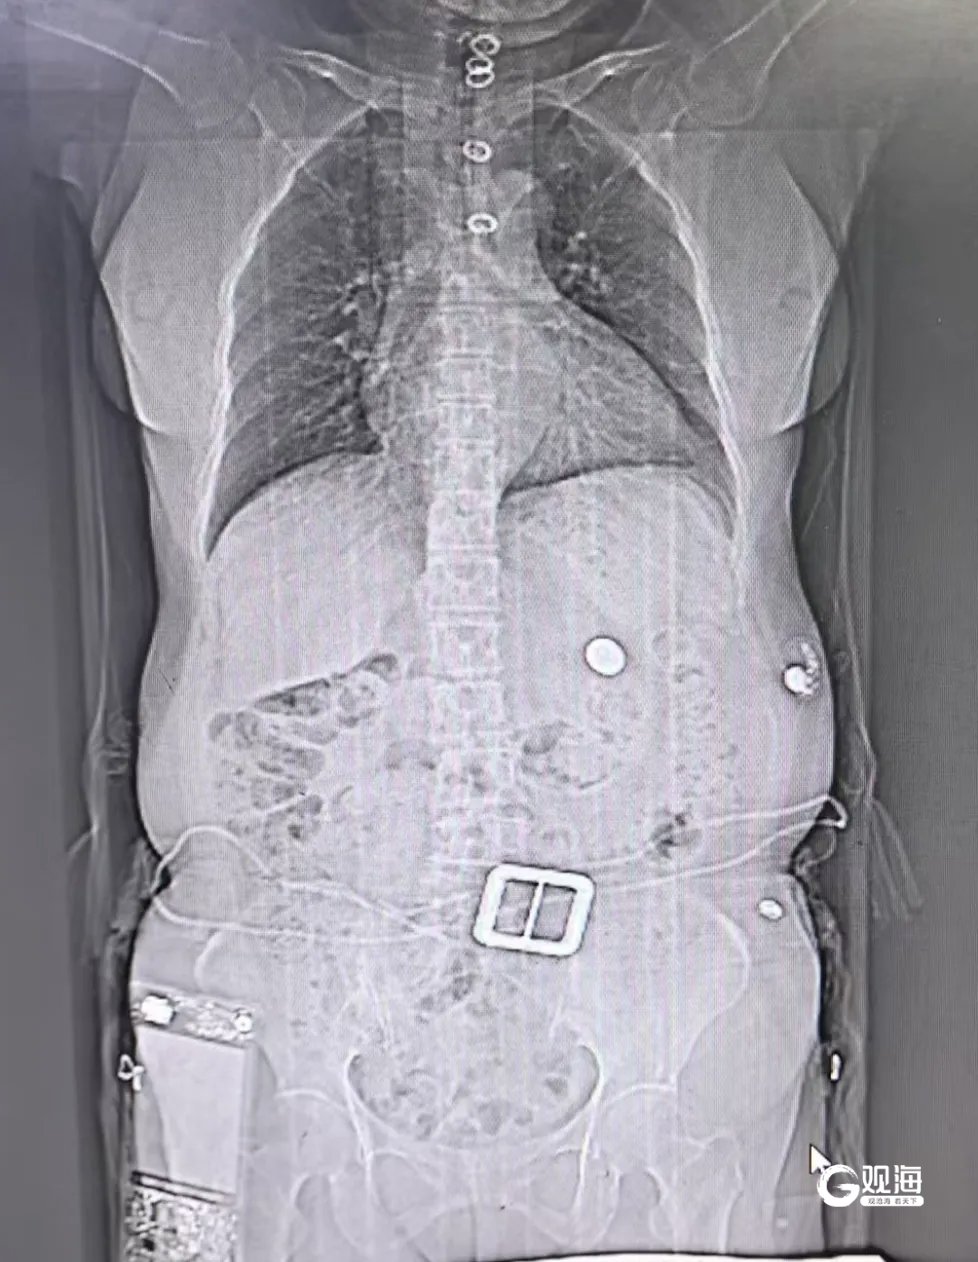

家人回忆,清点饺子里的硬币时发现少了一枚,才意识到老人可能误吞了硬币,随即紧急送医。消化内科内镜团队与麻醉科医生迅速集结。术前为患者行腹部CT提示胃内异物,考虑到老人年事已高,且有高血压、冠心病、糖尿病病史,麻醉团队采用精准静脉麻醉,确保老人在无痛、生命体征平稳的状态下接受手术;内镜医生则凭借高清内镜设备,清晰定位硬币位置,选用特制网篮器械,小心翼翼地套住光滑的硬币边缘,在避免损伤消化道黏膜的前提下,缓慢将硬币与内镜一同取出。整个手术仅用时10分钟,全程无创伤、出血。

主刀医生介绍,食管有三处天然狭窄,硬币容易卡在最上端的食管入口下方,此处紧邻气管和大血管,操作难度极大,稍有不慎就可能引发严重并发症。硬币在胃内同食物混在在一起,为术中寻找硬币带来困难,而且有误吸的风险,术后经检查,老人食管黏膜仅轻微充血,无穿孔、出血情况。